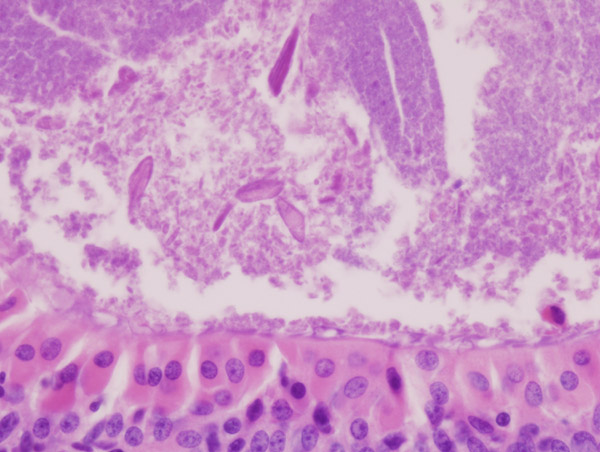

Mucoepidermoid Carcinoma

Mucoepidermoid carcinoma is a malignant tumor made up of squamous and mucin-producing cells.

Mucoepidermoid carcinoma is the most common malignant tumor of the salivary gland.

Mucoepidermoid carcinoma often occurs in the parotid.

The facial nerve is frequently compromised by mucoepidermoid carcinoma.